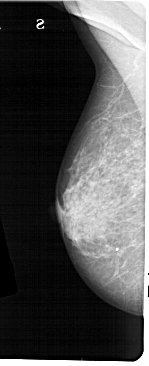

A_1473_1.LEFT_MLO

LEFT_MLO LINES 5476 PIXELS_PER_LINE 2221 BITS_PER_PIXEL 12 RESOLUTION 43.5 NON_OVERLAY